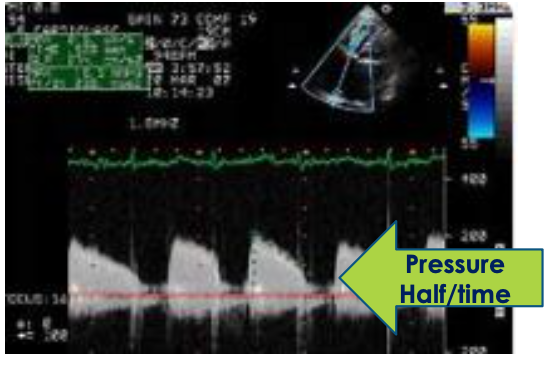

17

Q

Tricuspid Stenosis

Quantification

Explain how to obtain pressure half time and TVA

A

• Compare PLAX RVIT, PSAX RVIT, A4C, A3C RVIT (modified view), Subcostal 4C/SAX if necessary

• Optimize Doppler angle

• CWD focus within the TV leaflets

• increase sweep speed to 100 mm/s

• Acquire the peak TS waveform, freeze, and measure from the peak velocity down to the deceleration slope *average 3+ waveforms

• The machine will calculate the P½t and TVA once the slope is acquired

18

TVA equation

TVA = 190/pressure half time

*190 is constant

19

Similar to MS, TS has an ______ peak velocity (E), _______ EF slope, and _____ A wave that assessed via the pressure half time

increased

flattened

absent